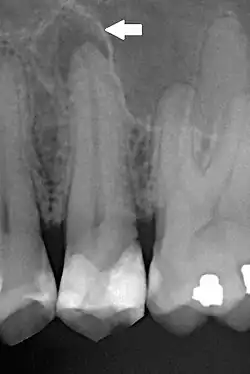

Dla lekarza stomatologa pomocny w zdiagnozowaniu zapalenia tkanek okołowierzchołkowych może być wywiad, dodatni objaw Owińskiego oraz badanie RTG.